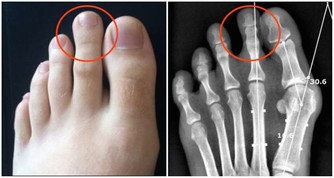

那麼,怎麼才能知道你是否有靜脈曲張呢?很多人覺得靜脈曲張很好辨認,因為你能看到腿部出現突出的凸出靜脈,跟蚯蚓似的。根據靜脈曲張的深度,那些“蚯蚓”可能是藍色、綠色甚至無色。

然而,在出現並發症之前,多達一半的靜脈曲張患者都沒有明顯的病情跡象,因為許多有問題的靜脈仍隱藏在皮膚下,在檢查中才可以看到。但如果你仔細觀察,憑藉肉眼,我們也能發現靜脈曲張的跡象。

2. 站立時最容易在皮膚下看到的增大的蚯蚓狀藍色靜脈;